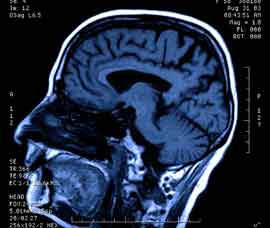

MS is a neurological condition that affects around 100,000 people in the UK. It can cause vision problems, difficulties with walking and fatigue, and tends to strike mainly young and middle-aged women.

The new research, which is published in the journal Neurology, looked at post mortem brains of MS patients, examining areas where neurological damage had recently occurred.

Dr Meier and her team of collaborators found that, although the virus was not actively spreading, it was releasing a chemical message into areas of the brain nearby. This chemical message - made up of small RNA molecules - was activating the body’s immune system, causing inflammation. This damages nerve cells in the brain and causes MS symptoms.